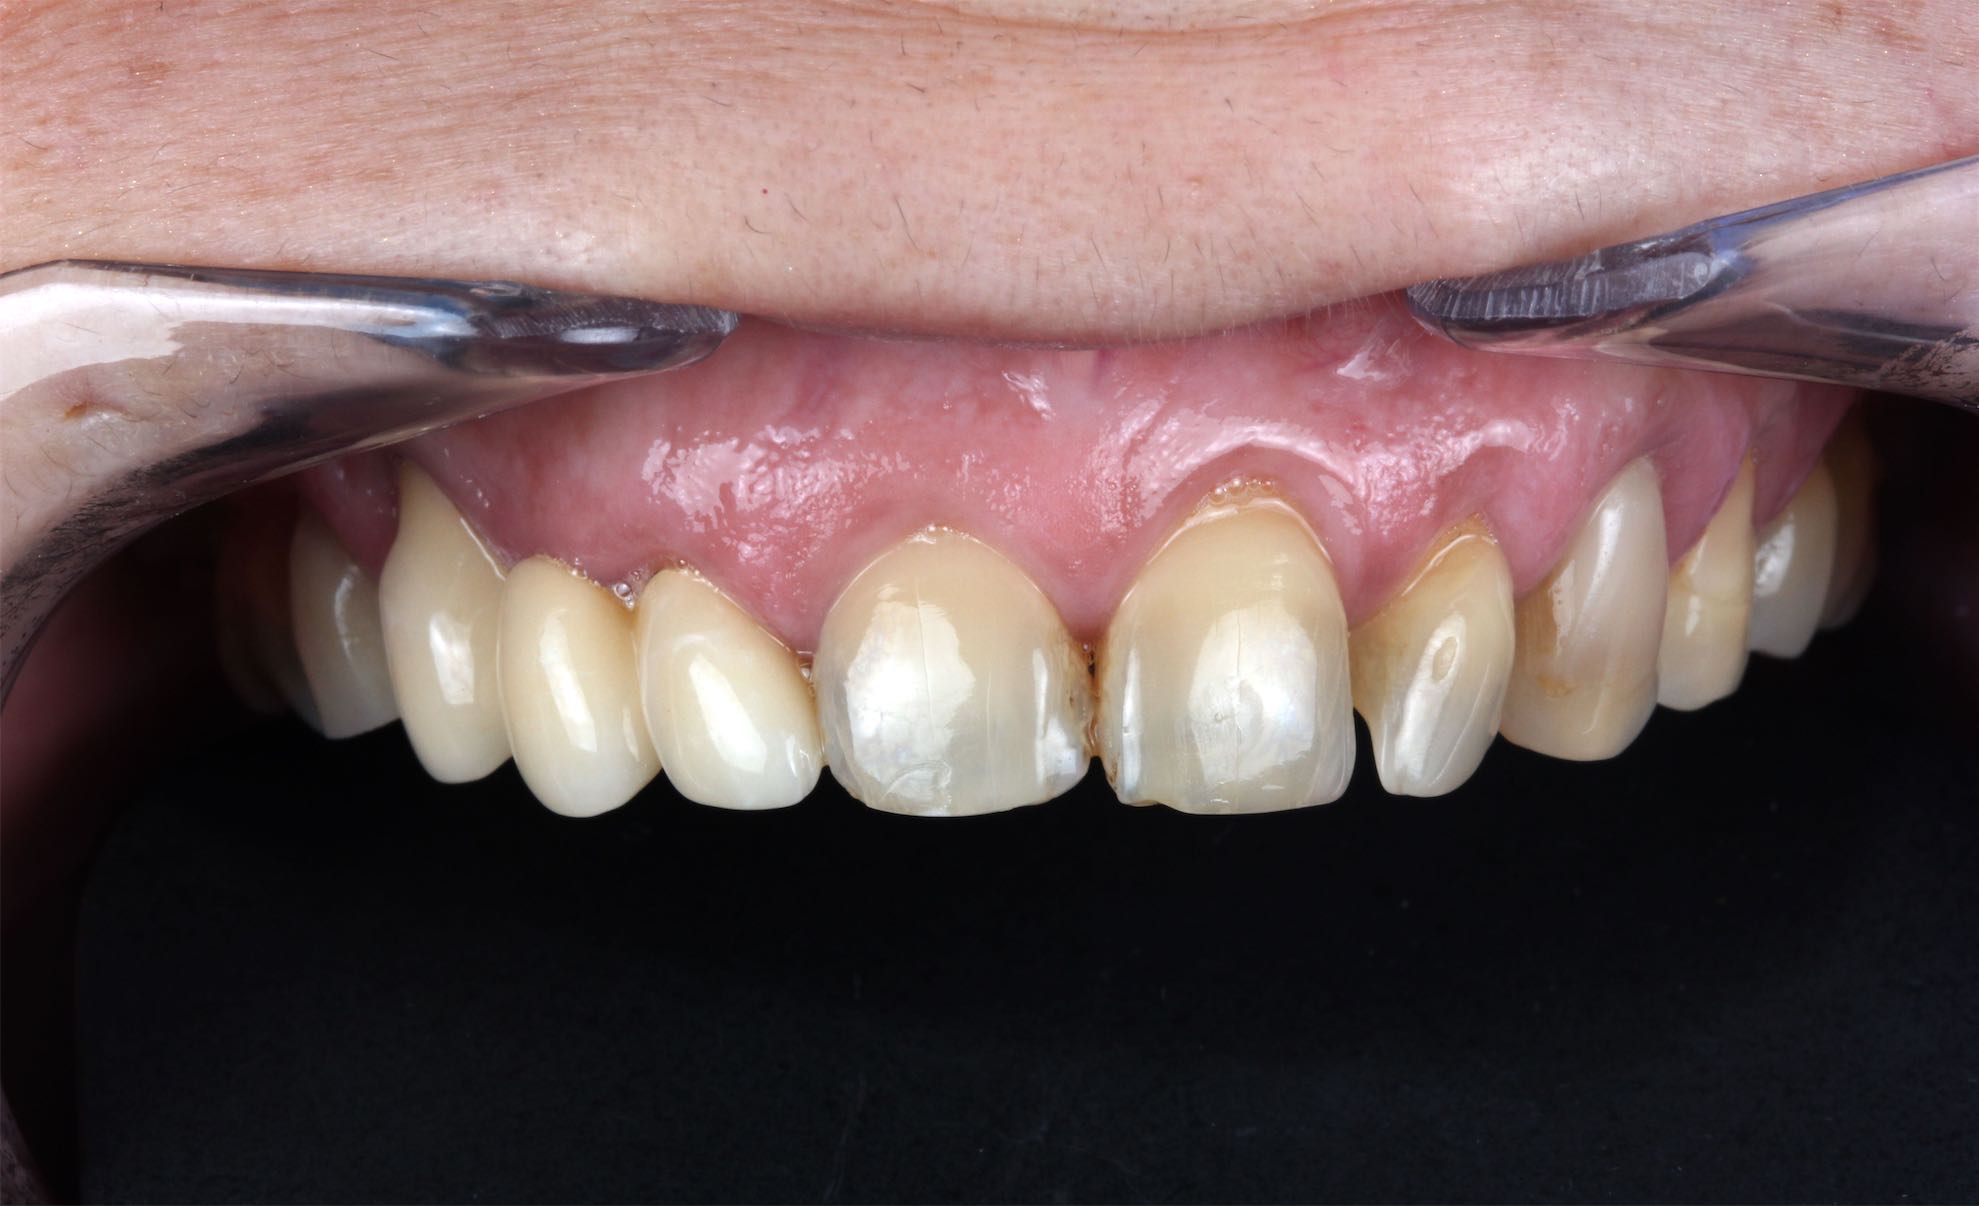

Caso de Rehabilitación completa y aumento de DV

BeforeAfter